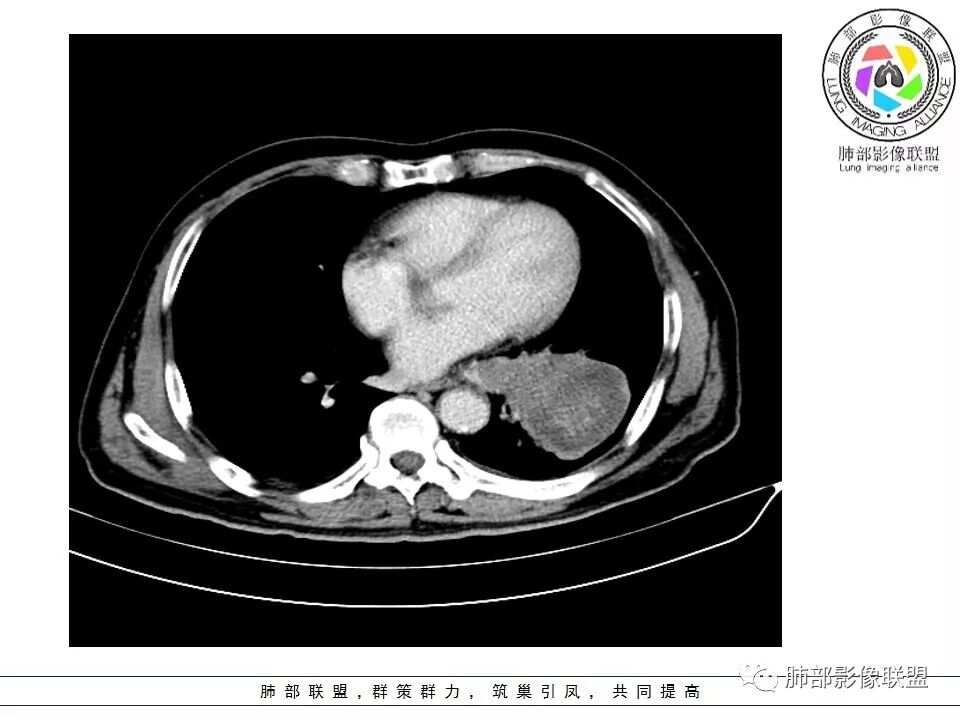

老年男性咳嗽,左下近肺门团块影,不规则强化伴坏死,左下肺静脉、支气管旁淋巴结转移受压、并侵犯左下支气管,考虑鳞癌,鉴别小细胞。

男,70岁,左下肺肿块影,分叶,增强有较大范围坏死,左肺门肿块影,跨叶,包绕支气管与肺门血管,致其狭窄考虑为淋巴结肿大,综合考虑为恶性肿块,鳞癌并左肺门淋巴结转移

肺门淋巴结有肿大,支气管内有肿物,这么大病灶没有坏死,我考虑神经内分泌癌或者小细胞肺癌。鳞癌不符合没看到明显阻塞

老年男性,咳嗽主诉,胸部ct左侧肺门新生物,支气管阻塞,不均匀强化,伴淋巴结肿大,考虑鳞癌,鉴别小细胞肺癌。

老年男性,左下占位,类圆丶浅分叶,无毛刺及胸膜凹陷征,各支气管狭窄,增强不均匀强化,左肺门淋巴结肿大考虑恶性,小>鳞

患者老年男性,以咳嗽就诊,胸CT:左肺下叶占位,病灶呈膨胀性生长,左肺下叶气管明显狭窄,病灶边缘光滑,并可见分叶,增强可见病灶内低密度区,病灶边缘强化。考虑恶性,鳞?肉瘤?

左下肺团块影,不规则强化伴坏死,左下肺静脉、支气管旁淋巴结转移,并侵犯左下支气管,考虑恶性病变,小细胞?

左肺主支气管下肿块,病变包绕并向腔内生长,无阻塞性肺炎,内部可见穿行血管,增强后可见实性明显强化,纵隔淋巴结肿大,老年男性,考虑:神经内分泌癌(类癌、小细胞癌),淋巴瘤,鳞癌

病史:男,70岁,咳嗽;影像:肺门淋巴结,淋巴结内血管毛糙不规则,静脉期,转移大,左心房左下静脉下支是否有累及。主体病灶,呈扇形,沼泽样,指状突起。肺气肿并不明显,左侧少许,左上叶支气管狭窄,肺窗点状凸起,纵膈窗并没有,考虑淋巴结压迫所致。老王曾经说过,小细胞来不及跑得快,胸膜目前没有积液是否是这个原因?诊断:恶性,小细胞肺癌;鉴别:鳞癌,不太像,其他神经类分泌恶性肿瘤;处置:经皮穿刺或EBUS。

左下肺占位性病变,伴肺门淋巴结肿大,强化示不均匀明显强化,可见边界不清坏死区,考虑恶性肿瘤!病灶缺乏分叶及毛刺,整体圆顿,病理倾向大细胞!

左下肺肿块,不均匀强化,其内可见坏死或粘液,更多考虑坏死,左下肺支气管堵塞,左肺门多发肿大淋巴结,左下肺癌,鳞癌可能性大鉴别于小细胞癌

病灶从外向里长,气管狭窄,血管受侵犯,肺门纵膈淋巴结肿大,考虑恶性,首先考虑小细胞癌

左下肺占位伴肺门淋巴结肿大,病灶呈膨胀性生长,左肺下叶气管明显狭窄推移,病灶边缘光滑,并可见分叶,增强可见坏死,病灶边缘强化,阻塞性肺炎不明显,恶性没问题,考虑低分化腺癌,鉴别神经内分泌肿瘤,无冰冻感觉,坏死明显,小细胞不支持,排除大细胞与类癌

老年男性,症状轻。左肺下叶类圆形肿块,边界清楚,分叶不明显,其内无空泡征,边缘无毛刺及胸膜牵拉,远端无阻塞性肺炎。左肺门影增大。增强扫描左肺下叶肿块可疑轻度强化(无平扫对比),局部见小尾巴征。左肺门区见不规则形团块,似多个结节融合,肺动脉受压穿行于病灶中,形成冰冻肺门感觉,局部层面似见肺门区团块与左肺下叶肿块相连。综合考虑小细胞肺癌(SCLC)。

左肺下叶肿块,边缘膨隆,分叶略浅,占位效应明显,远端没有明显花花草草,其内部不均匀强化,坏死边界不清,可见受累的强化血管穿行,是否有钙化?没有平扫,不清楚;同侧肺门淋巴结受累,包绕支气管生长,并突入下叶支气管,导致管腔闭塞及狭窄,考虑恶性没问题,肿瘤既有由外向内生长侵犯又有冰山征的感觉,小>类癌>低分化腺>鳞

病灶从外向内生长,气管狭窄,血管受侵犯,肺门纵膈淋巴结肿大,考虑恶性,腺癌。鉴别小细胞肺癌。

左下肺占位,边缘分叶彭隆,远端无明显阻塞性炎性,考虑外朝内生长为主,增强扫描边缘及病灶内均可见强化,血管破坏。考虑恶性,间叶组织来源,肉瘤?

左肺下叶肿块,内部坏死明显,整体从外向内生长,下叶支气管及舌叶支气管被包绕生长,肺门区淋巴结肿大,坏死。远端无明显阻塞及不张,综合来看,恶性肯定,肺癌,整个病灶有分别有支持小细胞、鳞癌,腺癌及肉瘤样癌的地方,但又不典型,以低分化腺癌或肉瘤样癌或混合性癌(腺癌小细胞混合,低化分腺鳞癌混合),神经内分泌癌可能性大,单纯的鳞癌或小细胞癌有可能,但确实不典型了。至于间叶来源的恶性肿瘤,很少这样从向外内生甚至包绕支气管壁生长,再加上相对罕见,可能性小。

腔外浸润为主,腔内无明显堵塞,原发肿块推移支气管为主,边缘光滑,轻微分叶,肺门引流区淋巴结肿大,而纵隔淋巴结无明确受累,综合考虑,癌:低分化腺癌?大细胞癌?肉瘤样癌?间叶组织肿瘤:肺肉瘤,罕见

左肺门乱乱的,有血管受压表现,有支气管腔内占位表现,肺门淋巴结肿大肯定是有的;左肺下叶见一巨大包块,边缘光滑,内侧又一个切迹,考虑是病变受到了小叶间隔阻挡造成的其内部大部分不强化,但有局部一小片强化;壁不均匀环形强化,总体较薄;周围没有阻塞性肺炎,感染性病变应该是不考虑的,因为周围清楚,也没有感染的症状,还是考虑肿瘤性病变;关键是它边缘光滑,内部应该是坏死,但有强化提示坏死不彻底,这么大了,边缘恶性征象不明显,不符合腺癌,鳞癌呢也不太符合,阻塞性肺炎没有,坏死太明显了,这么大,边缘光滑,坏死明显,符合肉瘤和肉瘤样癌,不除外小细胞肺癌

南边:病灶分为两大块,外围囊实性大肿块,支气管关系不密切,内带多发淋巴结,侵犯支气管、肺血管,恶性没问题,按理间叶为主,或不典型的癌,这不是一个中央型的肺癌,是外朝内进展的,奇怪的是边界这么清楚光滑,一般癌肉瘤、肉瘤类多,其次才是癌,远端也没有阻塞,大方向是这样,恶性,间叶来源?或者混合,恶性程度较高,鉴别就是结核,因为结核是妖

1.左肺下叶近肺门区肿块,肿块外围大,内带小,提示外围向中央生长,符合周围型SCLC沿支气管方向生长。

2.病灶边缘光滑,未见明显分叶、毛刺,符合神经内分泌癌、癌肉瘤及间叶来源肿瘤。

3.病灶内密度偏低,穿行血管未见明显异常,轻度不均匀强化,为乏血供病灶。病灶内可疑坏死区,未见空洞;乏血供符合SCLC,但坏死区不符合。

4.病灶区支气管以受压推移为主,管腔不规则,腔内通而不畅,提示病灶粘膜下为主,符合SCLC迁徙蔓延或间叶来源肿瘤。

5.病灶内有血管走行,血管局部受压,但是强化考虑为乏血供,提示病灶内肺动脉并不是供血血管,只是病灶侵袭性强把血管包埋而已,为血管包埋征;血流面光滑,血管包埋符合SCLC。

6.左肺门淋巴结肿大,与病灶局部融合分界不清,呈冰冻肺门;而纵隔内未见肿大淋巴结,冰冻肺门符合SCLC,但是病灶主体那么大,纵隔内没有明显肿大淋巴结,不是很符合SCLC娘小崽大的特点。

7.未见明显阻塞性炎症及阻塞性肺不张,更加提示病灶从外围向中央侵犯,符合SCLC罕见阻塞性肺不张。